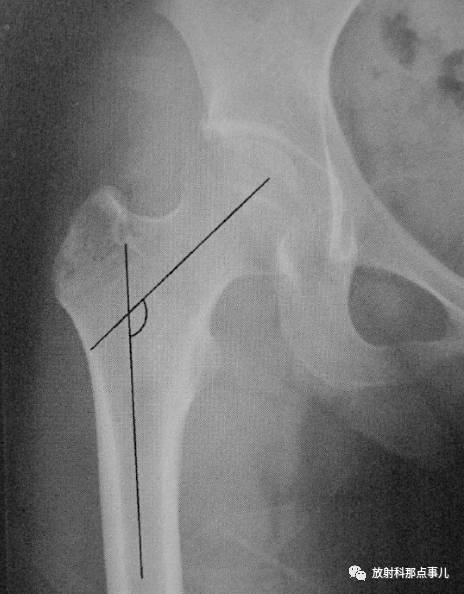

髋关节正位片上,股骨颈的长轴与股骨干纵轴之间形成的角度称为颈干角,又称内倾角。正常值在110—140°之间,男性平均为132°,女性平均为127°。颈干角随年龄的增大而减小,儿童的颈干角大于成年人,儿童平均为151°。颈干角大于正常值为髋外翻,小于正常值为髋内翻。

髋关节侧位片上,股骨颈纵轴线与股骨干纵轴线所成的夹角,新生儿正常35° ,成人为12° ~15° ,平均12.31° 。临床上股骨颈骨折应根据次标准复位。